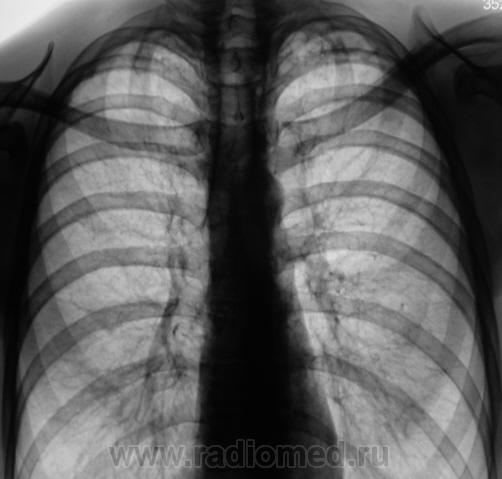

В 2009 году взяли пациента на контроль стандартно дообследовали.

Картинка была типичной, отправили на консультацию к фтизиатру, сделали все необходимые "отметки" в журналах и компе и успокоились, по поводу пациента.

Однако, в 2010 году пациент высвечивается, как прошедший профилактическую флюшку. Звоню к фтизиатрам, мол, что-же Вы братья по разуму "тубаря" на флюшку направили?

Оказалось, что была сделана интересная запись - "Данных за активный туб. процесс не выявлено", объяснили, что МБТ в мокроте не были обнаружены, а что там было в баночке, возможно, половино "слюны", так то неизвестно...

Сравнили две "8" за 2009 и 2010 годы, и вновь, направили пациента на консультацию к фтизиатру.